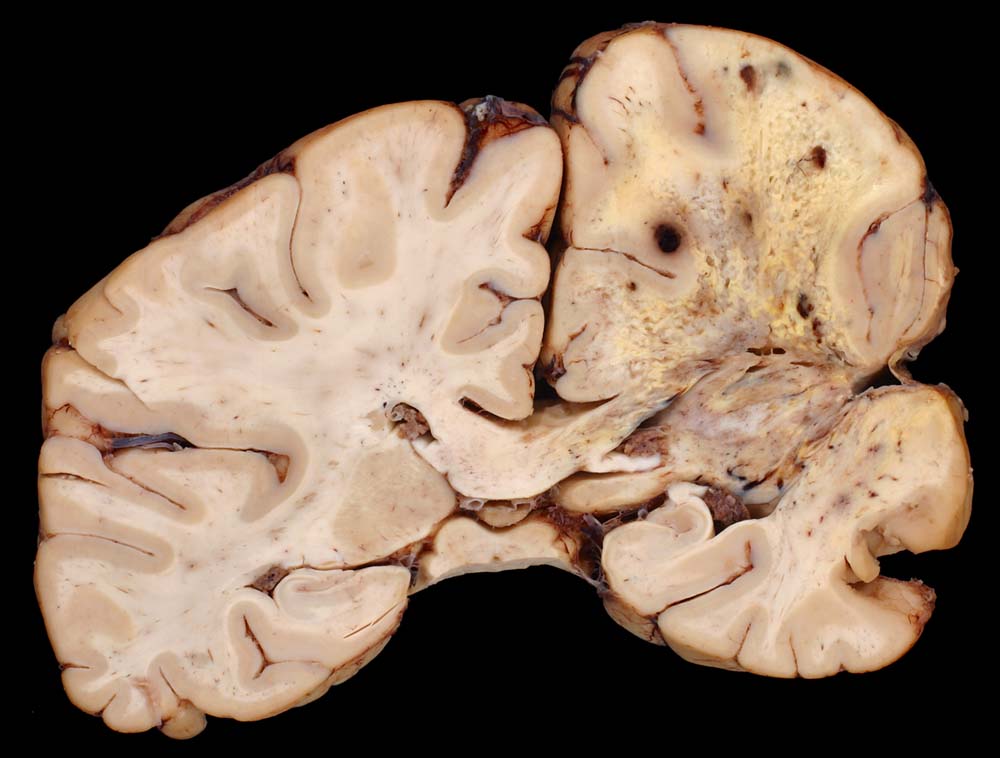

Bevorzugte Lokalisationen sind das Marklager des Frontal- und Temporallappens. Glioblastome des Hirnstammes sind selten und betreffen meist Kinder. Von dort breiten sie sich oft über den Balken schmetterlingsförmig auf die Gegenseite aus. Weniger als 5% der Tumoren wachsen multizentrisch. Eine Aussaat in den Subarachnoidalraum mit Metastasierung über den Liquor findet sich selten. Noch rarer sind hämatogene Metastasen in extraneurale Organe.

Die Schnittfläche ist auffallend bunt. Dies ist bedingt durch ein Nebeneinander von graurotem vitalem Tumorgewebe, gelben Nekrosen, roten Einblutungen und gelegentlich grünlichen Gallertzysten.

• Zellreicher Tumor mit sehr unscharfer Begrenzung zum normalen Hirnparenchym (rechts unten).

• Typische streifenförmige Nekrosen mit randständiger Palisadierung der Tumorzellen.

• Im Zentrum der Nekrose thrombosierte Gefässe umgeben von einem Saum vitaler Tumorzellen.